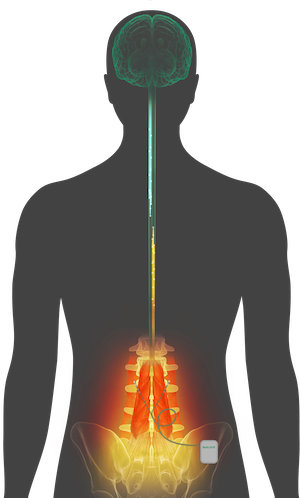

Mechanical chronic low back pain results from an injury or stress on the tissues surrounding the spine, including soft tissues, muscles, bones, and joints. Often times, this type of pain is due to impaired neuromuscular control and neural inhibition of the multifidus, which is the largest stabilizing muscle in your back.

ReActiv8 is the first and only restorative treatment option for mechanical chronic low back pain as a result of multifidus dysfunction, and aims to restore the neuromuscular control between the brain and spine.

The ReActiv8 device is implanted underneath the skin during a minimally invasive outpatient procedure:

- A generator is connected to two electrical leads, which are positioned to stimulate the nerves that control your multifidus muscle.